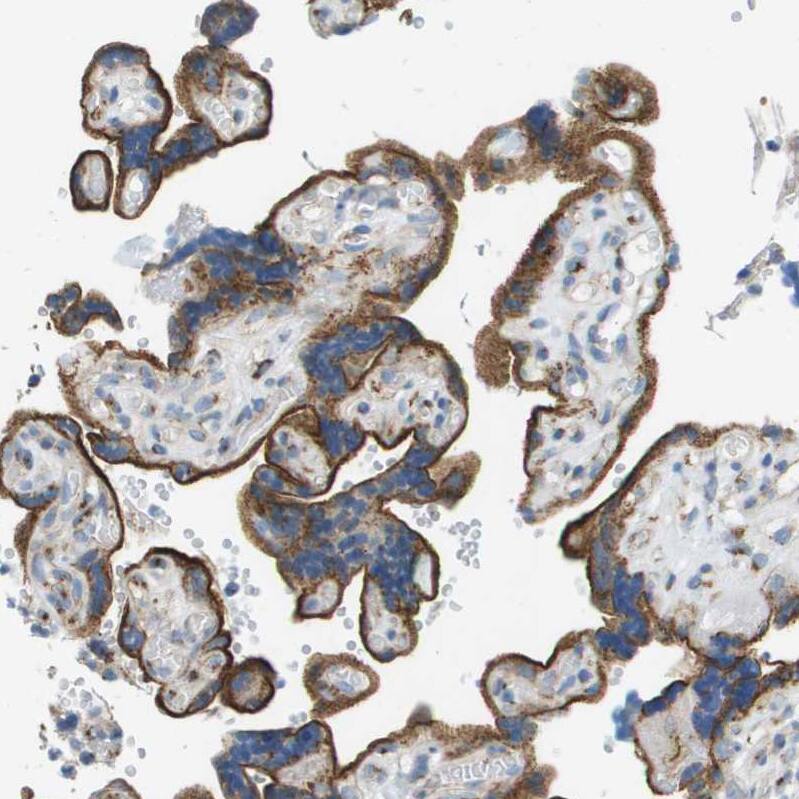

Staining of human cerebral cortex shows strong granular cytoplasmic positivity in neurons.Immunohistochemistry-Paraffin: ACBD3 Antibody - BSA Free [NBP1-83379]

Staining of human placenta shows strong granular cytoplasmic positivity in trophoblastic cells.Applications for ACBD3 Antibody - BSA Free